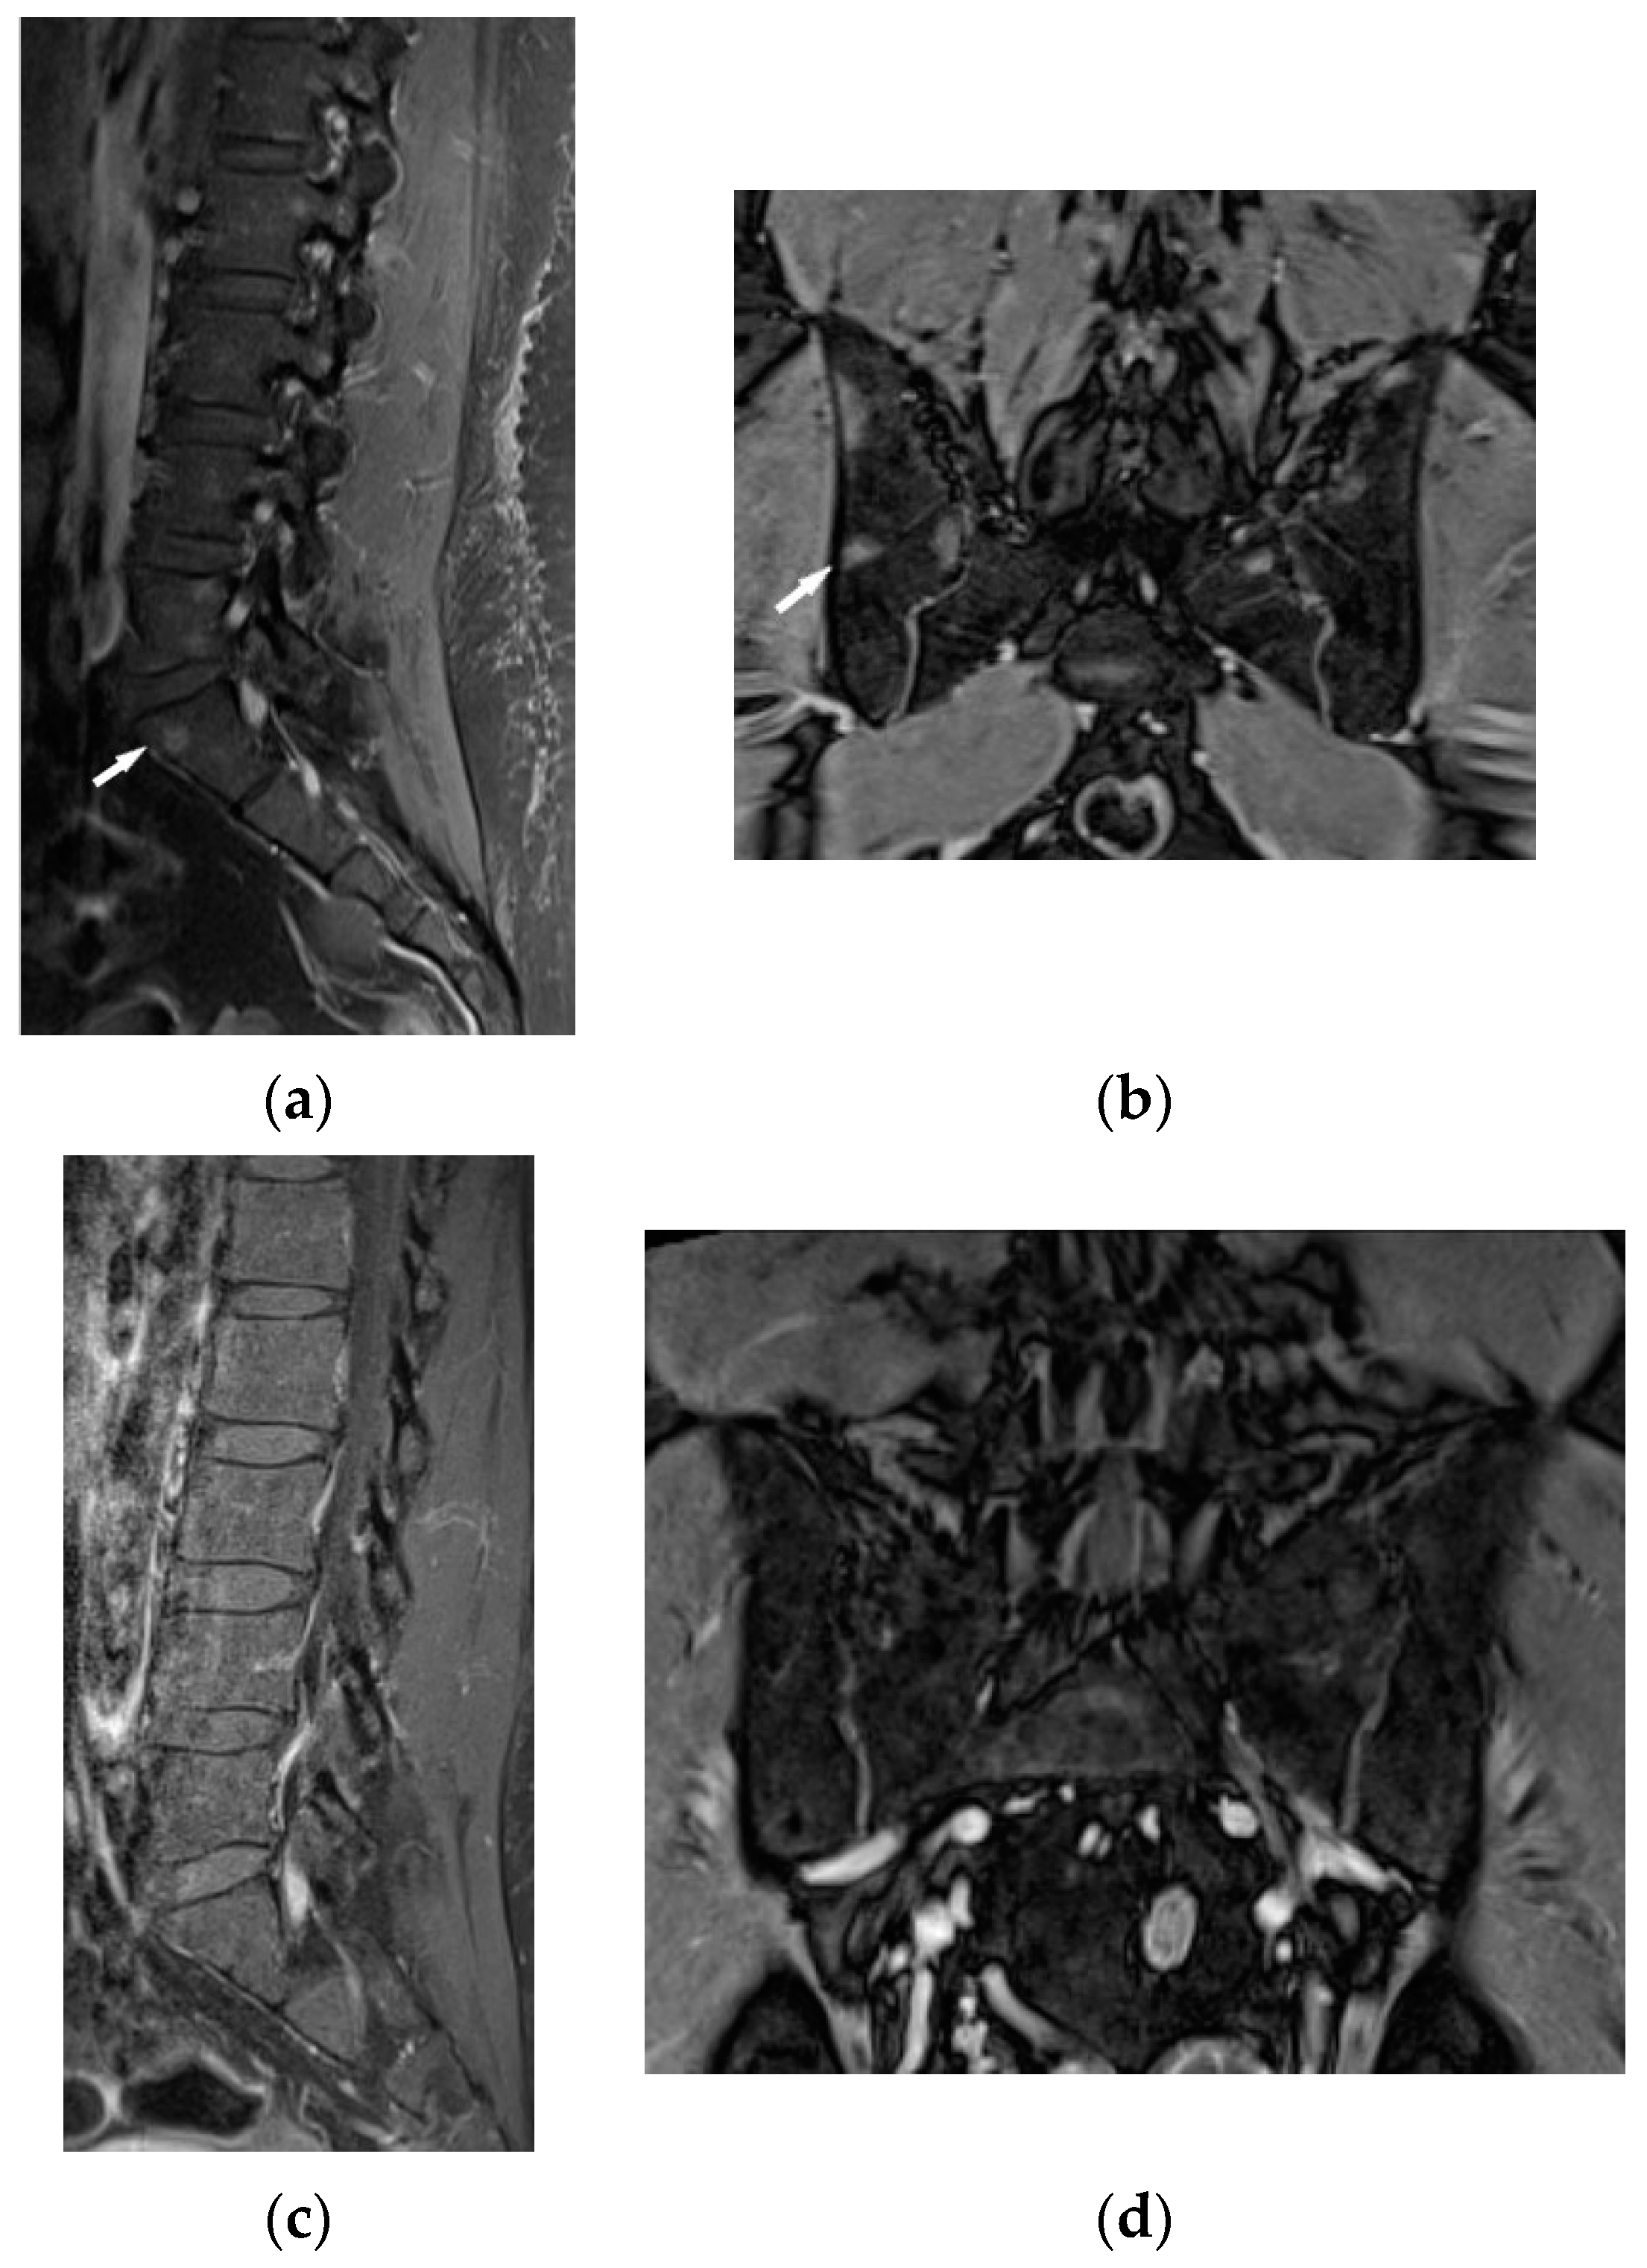

The lumbar spine MRI revealed protrusion of an intervertebral disc with compression on the dural sac and nerve roots, which presumably caused the symptoms. Moreover, the images of lumbar vertebrae and pelvis showed disseminated, small enhancing lesions (Figure 11a,b), which were isointense on T1- and T2-weighted images, hyperintense on TIRM images and revealed restricted water diffusion. The MRI appearance of the lesions was nonspecific. However, the radiologist interpreting the results had access to clinical data so the differential diagnosis took into account both sarcoidosis and metastases.

It was decided to repeat bronchoscopy. Pathological confirmation of sarcoidosis was obtained from a biopsy of the bronchial mucosa (non-necrotizing granulomas and multinucleated giant cells). To exclude other than sarcoidosis changes in the bones and bone marrow, the patient was consulted in hematology and orthopedic medical centers. Iliac bone biopsy revealed multinucleated giant cells and epithelioid granulomas without necrosis. In bone fragment-containing bone marrow, the image was suggestive of sarcoid granulomas as well. Due to confirmation of sarcoidosis with bone and bone marrow involvement and progression of lung disease, prednisone at a dose of 30 mg per day and methotrexate at a dose of 20 mg per week was implemented. As a result of treatment, almost complete regression of lung disease in the control chest CT, and normalization of respiratory parameters, was observed. Normalization of calcium level in 24-h urine test (Table 1), and regression of enlarged lymphatic abdominal nodes were also noted. Control MR imaging showed almost complete regression of intramedullary foci in lumbar vertebrae and complete regression of intramedullary foci in the pelvic bone elements (Figure 11c,d). Therefore, the dose of prednisone was gradually reduced to 10 mg per day and methotrexate to 10 mg per week.

Figure 11. 34-year-old patient. T1-weighted images, contrast enhanced, with fat saturation of the lumbar spine and pelvis. Multiple enhanced bone marrow lesions in the vertebral bodies ((a), white arrow) and in the pelvis at the level of the sacroiliac joints ((b), white arrow). Complete regression of the lesions after the treatment in the vertebral bodies (c) and pelvis (d).